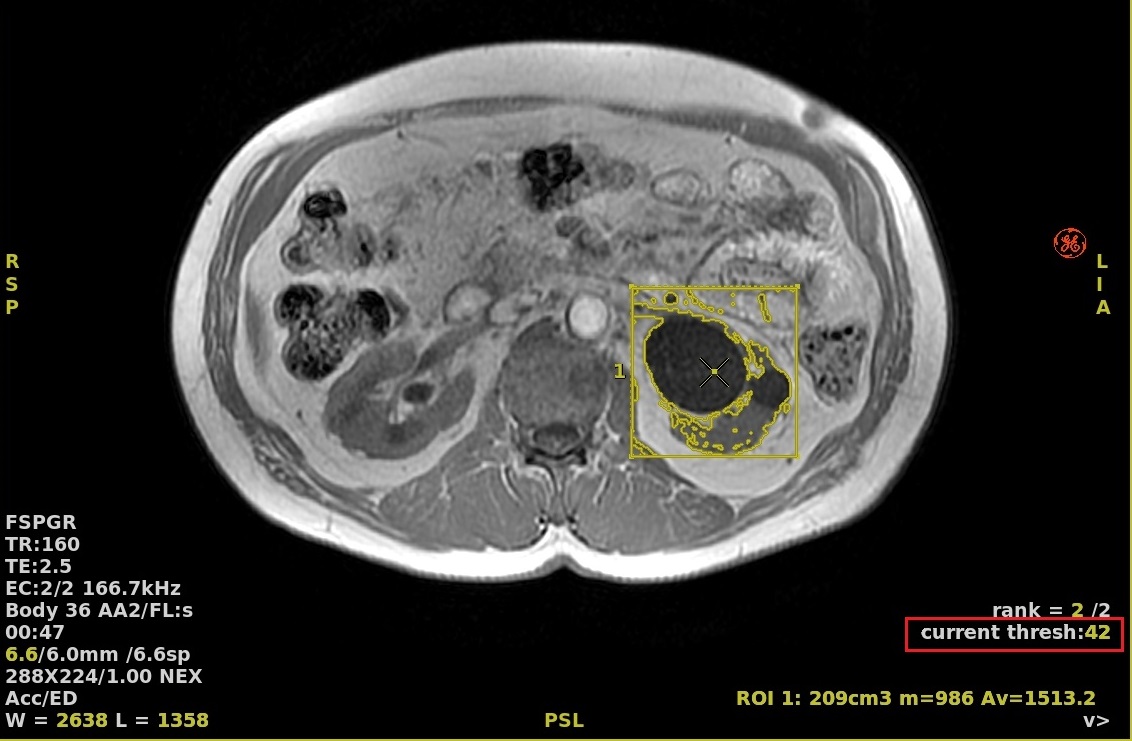

1. From the Auto Contour screen, click the Threshold option box and place the cursor in the center of the area of interest and left-click.

• This option is often used for functional images to calculate minimum, maximum, average, volume etc., values.

• A boundary box with a contour based on the maximum value contained within the box displays. To change the contour size, click and drag a end point handle in each corner.

Figure 2. Threshold option selected

• In the lower right corner, place the cursor over the active current threshold text and right-click to increase and left-click to decrease the threshold.

Figure 3. Active threshold text